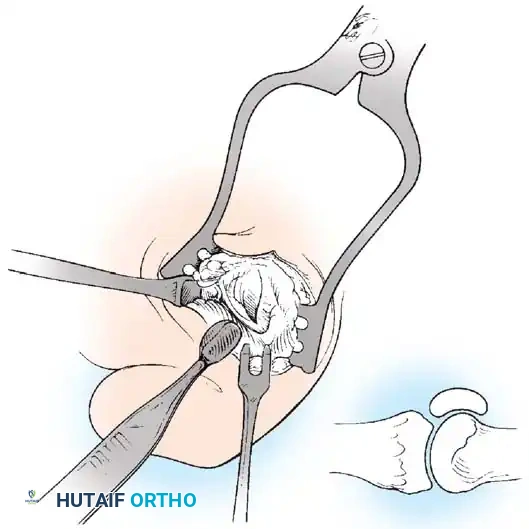

FIBULAR (LATERAL) SESAMOIDECTOMY: DORSAL APPROACH

• If after complete adductor hallucis release and preferably after a lateral capsular release, a fi bular sesamoidectomy is needed to correct the valgus deformity of the great toe fully, it should be done at this time.

• Adequately separate the fi rst and second metatarsal heads for exposure.

• Plantar fl ex the metatarsophalangeal joint 10 to 20 degrees, which reduces tension on the sesamoids.

• Grasp the fi bular sesamoid with a small Kocher clamp or sturdy tissue forceps, and pull it laterally into the intermetatarsal space (Fig. 78-20).

• Release the intersesamoid ligament. When this ligament has been incised, bring the fi bular sesamoid into the intermetatarsal space, where its removal is straightforward. Care must be taken when incising the intersesamoid ligament to avoid severing the fl exor hallucis longus tendon immediately plantar to it. If the tendon is severed, it probably should not be repaired at this level; loss of the tendon causes little if any functional impairment, and

Fig. 78-20 Modifi ed McBride procedure. Fibular sesamoid is removed.

FIBULAR SESAMOIDECTOMY: PLANTAR APPROACH

• If a plantar approach (Fig. 78-21A) is chosen for fi bular sesamoidectomy, have an assistant hold the ankle dorsifl exed, and use a headlight for seeing into the full depth of the wound. Avoid the fl exor hallucis longus tendon and the neurovascular bundle to the fi rst web space.

• Flex and extend the hallux, and inspect the radiograph to locate the sesamoid. Beginning 1 to 1.5 cm distal to the metatarsophalangeal joint, make a longitudinal incision in the plantar surface of the foot, extending the incision proximally 3.5 to 4 cm between the fi rst and second metatarsals.

• If the fi bular sesamoid requires excision, it usually is subluxed.

• When the skin and fascial septa within the forefoot pad have been separated, insert a small self-retaining retractor.

• Using small, blunt-tip dissecting scissors, identify the neurovascular bundle to the fi rst web space, and retract it laterally or medially, depending on the position of the sesamoid (Fig. 78-21B).

• Palpate the sesamoids, and fl ex and extend the hallux to locate the fl exor hallucis longus tendon.

• Open the pulley over the fl exor hallucis longus tendon, and retract the tendon medially. This maneuver is made easier by having an assistant hold the foot in dorsifl exion at the arch with one hand and fl ex the metatarsophalangeal joint to relax the fl exor hallucis longus tendon with the opposite hand.

• At this point, the intersesamoid ligament should come into view; divide it completely (Fig. 78-21C). This may require moving the scalpel 1 or 2 mm laterally or medially to fi nd the groove between the sesamoids.

• Incise the cleavage plane between the two sesamoids, while retracting the fl exor hallucis longus muscle medially and the neurovascular bundle laterally.

• Grasp the fi bular sesamoid with a strong pick-up or small Kocher clamp, and remove the lateral head insertion of the fl exor hallucis brevis muscle on the proximal end of the sesamoid using direct vision (loupe magnifi cation makes this easier, but is not necessary).

• When the medial and proximal restraints of the sesamoid have been released, sever the attachment of the adductor hallucis muscle to its lateral distal edge close to the bone with a scalpel or scissors.

• Sever the last attachment of the sesamoid distally where the plantar plate continues its distal insertion into the proximal phalanx (Fig. 78-21D).

• When the sesamoid has been removed, inspect the wound carefully for any bleeding. Pressing on the edges of the wound helps identify any potential bleeding vessels, which should be cauterized.

• Excising the sesamoid does not release the adductor insertion on the base of the proximal phalanx. This can be released through the plantar incision. Continuing to retract the neurovascular bundle laterally and the fl exor hallucis longus muscle medially, and adducting the hallux, while the opposite index fi nger palpates the adductor, helps identify the structure (Fig. 78-21E).

• Using right-angle retractors, expose the adductor, excise a small section of the tendon, and move the hallux medially.

• At the conclusion of this procedure, the surgeon should be unable to palpate any restraining structures on the fi bular side of the metatarsophalangeal joint. The transverse natatory fi bers in the dorsal aspect of the web space should be released manually. All restraints pulling the hallux laterally (except the extrinsic tendons) must be removed.

• Inspect the neurovascular bundle and the fl exor hallucis longus tendon.*

Fig. 78-21 Fibular sesamoidectomy (plantar approach). A, Incision. B, Common digital nerve to fi rst web space.